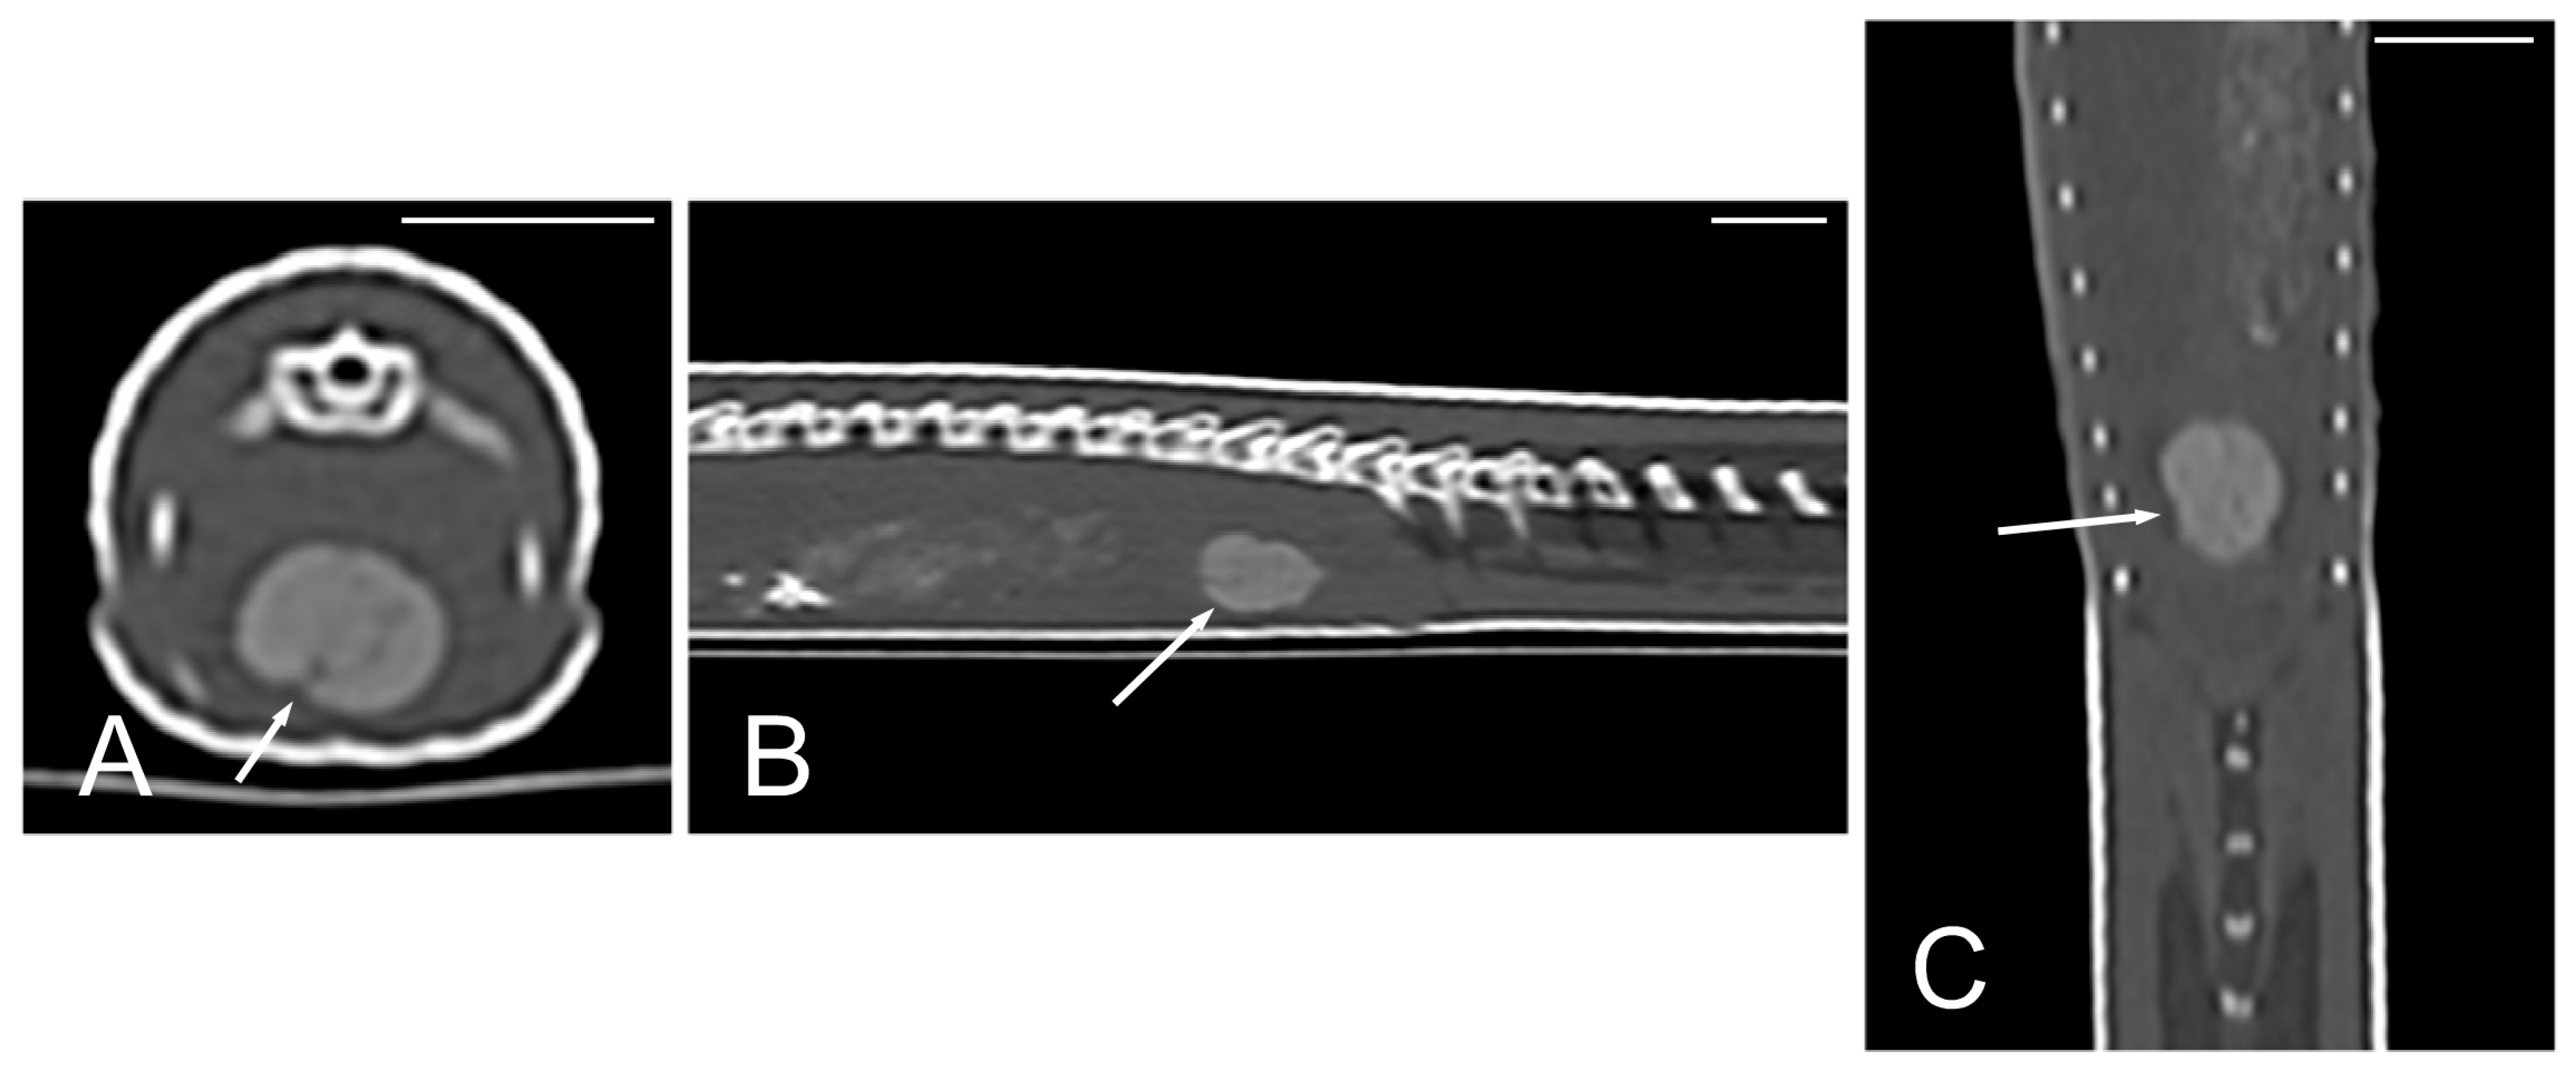

The kidneys and ovaries were identified only in postcontrast CT images. The kidneys appeared as a pair of soft tissue attenuating elongated structures in a ventrolateral position to the spine, in the caudal third of the coelomic cavity. They were best seen in the transverse and dorsal planes. Their margins were not well defined. The aorta was only seen in the midline between them (Figure 13). We could distinguish ovarian follicles only in one individual and they appeared as hypoattenuating rounded to oval structures, bounded by fine slightly hyperattenuating margins (Figure 14). The ureters, urinary bladder, oviducts, testes, and hemipenes were not recognizable in our CT studies.

Figure 13.

The postcontrast CT images of Pseudopus apodus in the dorsal (A) and transverse (B) planes showing both kidneys (white arrows) and the aorta (black arrow) between them in the dorsal part of the coelomic cavity, just ventral to the spine. Bar = 10 mm.

Figure 14.

The postcontrast CT images of Pseudopus apodus in the dorsal (A) and sagittal (B) planes showing ovarian follicles (arrows), just cranial to the kidney. In image A, the aorta (black arrowhead) is identified in the midline. In image B, the white arrowhead points to the right kidney. Bar = 10 mm.

The cloaca was identified in the caudoventral part of the coelom in only two animals due to the presence of hyperattenuating content in the lumen (urate salts) (Figure 15).

Figure 15.

The CT images of Pseudopus apodus in the transverse (A), sagittal (B), and dorsal (C) planes showing hyperattenuating content (urate salts) (arrows) in the cloaca. Bar = 10 mm.